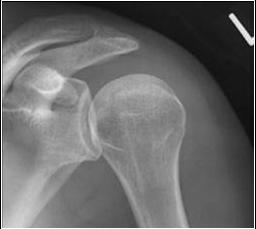

Normal Shoulder

Rim sign

widened joint space between anterior rim of glenoid and humeral head

Posterior dislocation